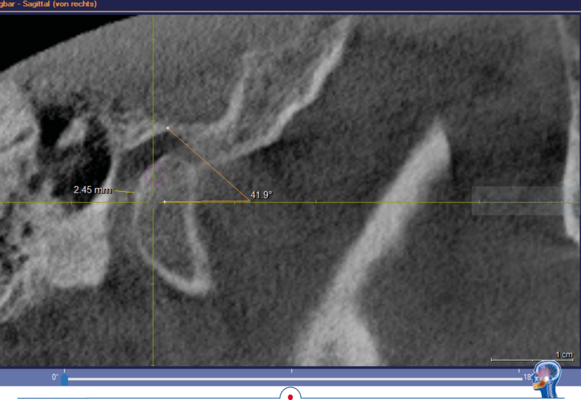

Grundsätzlich ist es logisch, dass die habituelle Okklusion den Patienten in

seine jeweilige Kondylenposition „zwingt“. Das kann man sehr schön bei einer

DVT-Aufnahme erkennen, wenn diese ohne frontalen Aufbiss in habitueller Okklusion realisiert wird.

In dem DVT wird sichtbar, dass der linke Kondylus in habitueller Bisslage um

ca. 2,5 mm deutlich zu anterior positioniert ist. Ursache dafür ist der Zahnkontakt bei 26 und 36. Dieser Zahnkontakt zwingt den Unterkiefer linksseitig in die anteriore Kondylenposition. Wenn jetzt in diesem Gebiss eine klassische Handbissnahme für eine Zahnversorgung durchgeführt wird, wird diese „falsche Kondylenposition“ in den Artikulator übertragen.

In dem hier vorgestellten Fall wurden diese Parameter zusätzlich im DVT bestimmt. Die im DVT ermittelte sagitale Gelenkbahnneigung beträgt rechts 41,9° und links 38,3°. Die mit Centric Guide® 3D ermittelte Gelenkbahnneigung beträgt rechts 43,86° und links 38,03°. Damit weichen die beiden Werte rechts nur um 1,96° und links nur um 0,27° voneinander ab. Wenn man sich die Gelenkbahneinstellung im Vollwertartikulator anschaut, stellt man schnell fest, dass diese nur in 5° Schritten erfolgt.